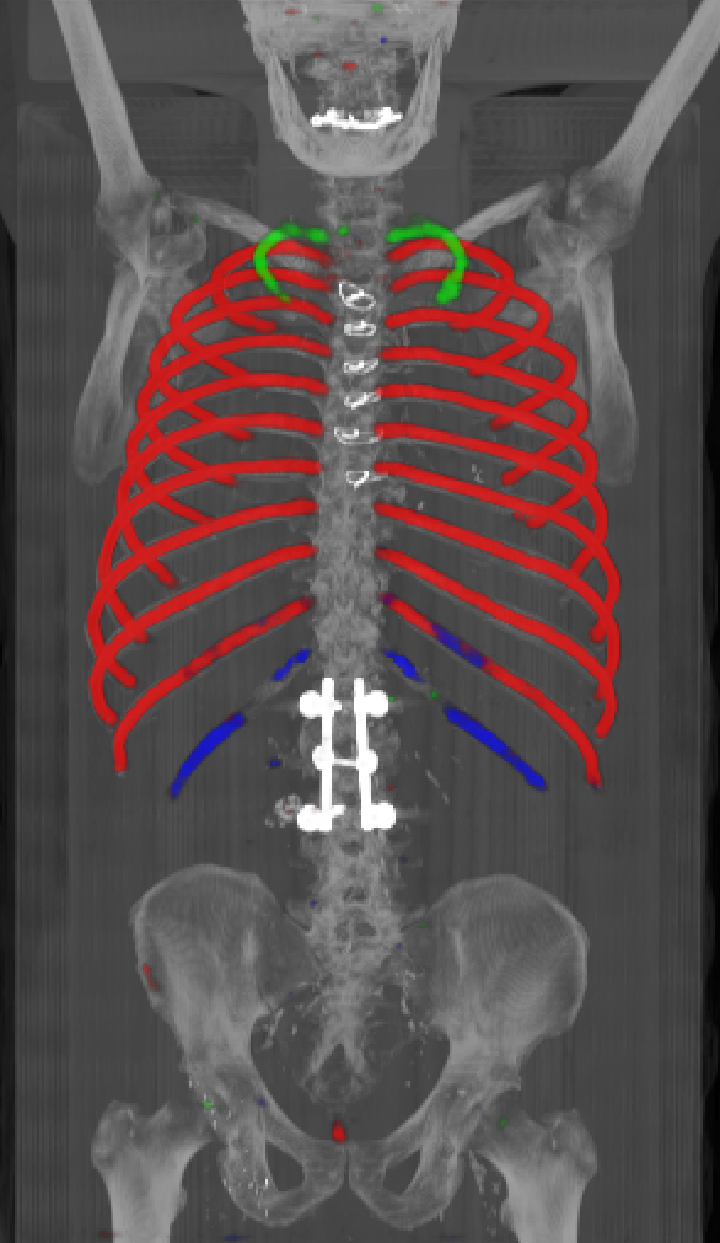

As can be seen from Table 2, we obtain overall good performance for the overall rib detection captured for example with an mean Dice of 0.84. Let us remark that for thin objects, such as the dilated rib centerlines, the Dice score constitutes a rather sensitive measure. The results indicate that detecting the first and twelfth rib pairs is more difficult for our network. While extraction of the first rib is more challenging due to, e.g., higher noise in the upper thorax or other bony structures in close vicinity (clavicle, shoulder blades, vertebrae), the twelfth rib can be extremely short and is easily confused by the neighboring ribs. For further illustration, Figure 4 shows the results on selected representative cases. Generally, the ribs are well detected without major false responses in other structures - despite all the different challenges present in the data. The color coding highlighting of the multi-label detection reveals that first and twelfth are mostly correctly detected. In few cases the network wrongly generated strong responses of the classes first rib or last rib for voxels belonging to the second or eleventh rib pair.

Refer to caption

Figure 4: Maximum intensity projections (MIP) of selected CT volumes overlaid with the multi-label output of the neural network (green: first rib; red: intermediate rib; blue: twelfth rib). The selected case above display common difficulties which are inherent in the data set, such as pads (a) or cables (b), internal devices such as pacemakers (c), stents (d), spinal (e) and femural/humeral implants (f), injected contrast agents (g), patient shape variations such as scoliosis (h), limited field of views (FOVs), i.e. partly missing first (i) or twelfth rib (j).